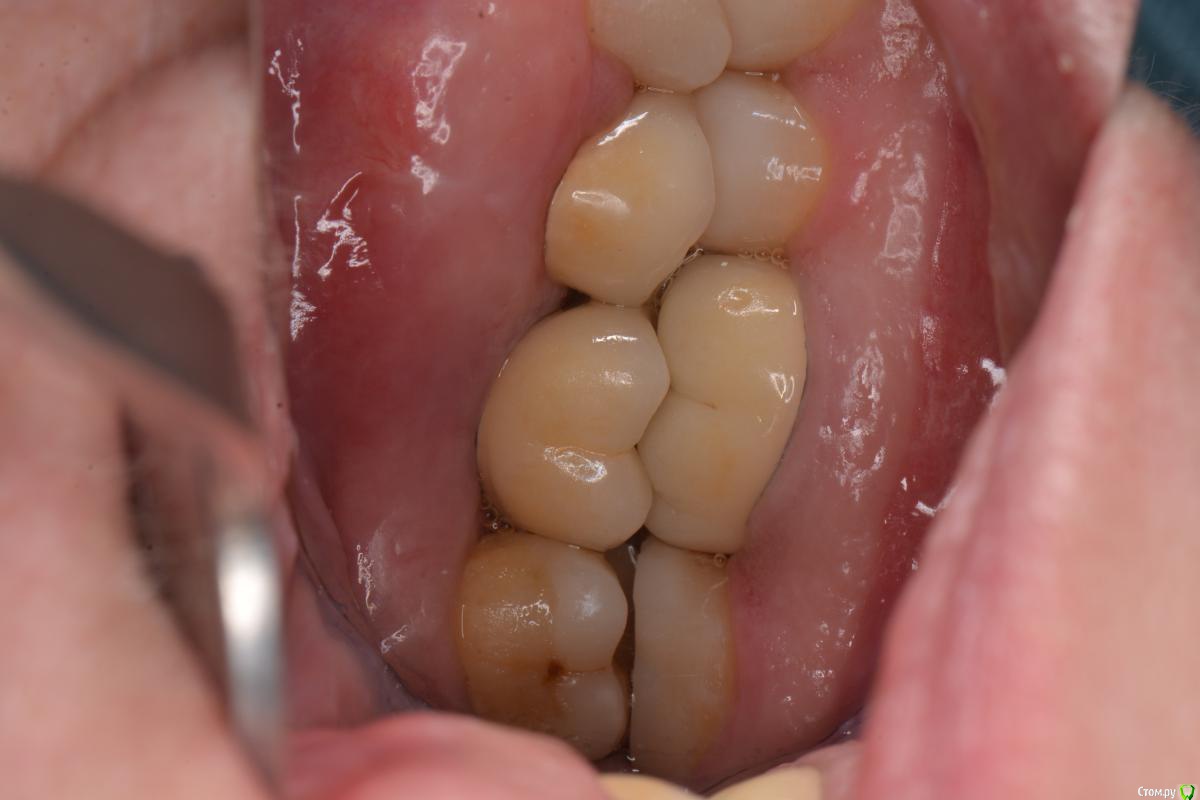

togrul Опубликовано 3 марта, 2015 Поделиться Опубликовано 3 марта, 2015 (изменено) Добрый вечер. Снимки в день сдачи. Изменено 3 марта, 2015 пользователем togrul 4 1 Ссылка на комментарий

Dr.Zoom Опубликовано 3 марта, 2015 Поделиться Опубликовано 3 марта, 2015 На винтовой фиксации?Есть показания для винтовой фиксации.Да, на винтовой фиксации. Толщина слизистой хорошая и цемент проблемно будет вычистить, да и контур прорезывания покрасивее можно сделать Ссылка на комментарий